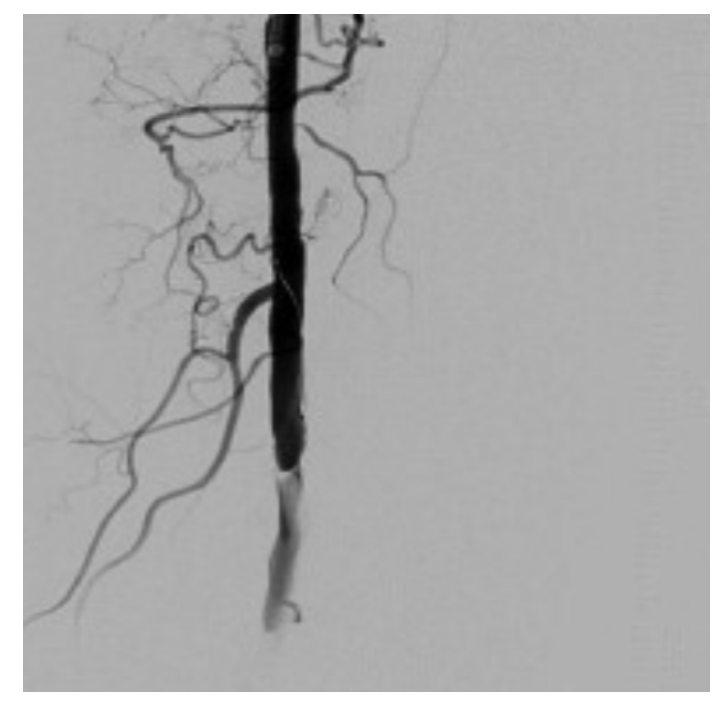

The patient was referred for invasive angiography. The vascular anatomy on the left lower extremity was unremarkable up to the distal popliteal artery, where an apparent dissection plane was noticed with Thrombolysis in Myocardial Infarction 1 flow (TIMI-1) (Figure 3). The false lumen had compressed the true lumen with minimal antegrade flow. This initial angiography was obtained with a diagnostic 6 French (F) catheter positioned in the mid superficial femoral artery.